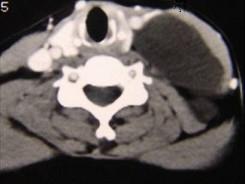

问题 男性,40岁,颈部出现无痛性囊性包块2年余,CT扫描如图所示,最可能诊断为 ( )

选项 A、神经源性肿瘤 B、颈动脉鞘瘤 C、血管瘤 D、淋巴结肿大 E、淋巴管瘤

答案 E